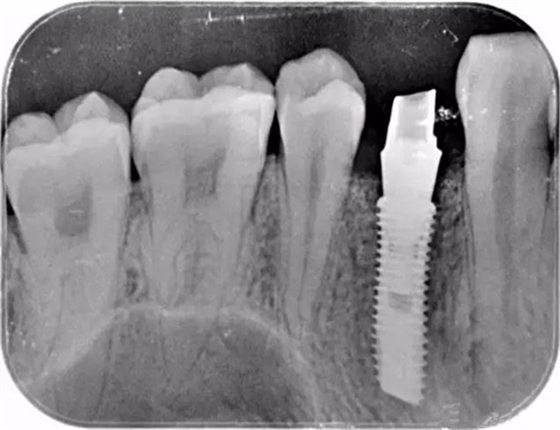

該顧客選擇的是登騰Superline種植體.因為顧客骨高骨寬條件很好,選擇種植4.0*12植體植入。術中發(fā)現(xiàn)頰側骨壁存在缺損,植入Biooss骨粉,加固種植體。從照片中可以看到基臺愈合之后的效果不錯。

這個是顧客術后旋入成品基臺的X片

種植牙修復后,種植體與牙槽骨緊密結合,種植牙與真牙外觀極其相似,上下牙咬合正常,種植體周邊無骨吸收情況。整個治療時長6個月,術后修復效果良好。